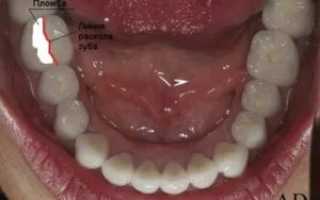

- Киста в слюнных железах, возникает редко, опухоль имеет полостное новообразование с жидким внутренним секретом. Часто проявляется в зоне малых слюнных желез, реже под языком. Патология включает в себя несколько видов болезни. Дермоидная форма заболевания имеет небольшую шишку белого или серого цвета. Не вызывает боли и дискомфорта. По мере увеличения в объеме мешает принимать и глотать пищу, влияет на произношение слов. Такая форма относится к врожденным аномалиям, лечение производится только хирургическим путем. Еще один вид кисты — ранула. Основной показатель — большой размер, в определенных ситуациях достигает 5 сантиметров. При самостоятельном прокалывании велик риск занести инфекцию. Поэтому лечение производится хирургическим путем. Часто бывают рецидивы. Чаще всего у пациентов встречается слизистая форма новообразования. Она отличается синеватым оттенком, безболезненностью. Размеры шишки не увеличиваются. После полного формирования шишки происходит ее разрыв и дальнейшее заживление слизистой под языком.